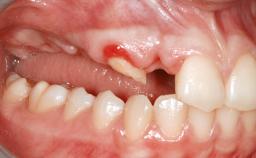

A 47-year-old woman who had suffered from aggressive periodontitis requiring a number of periodontal interventions over more than 10 years was referred by her general dental practitioner and periodontologist for bone augmentation and implant therapy. Her failing dentition had already been scheduled for extraction. The patient expressed a desire for implant-supported fixed restorations and esthetic improvement of her lower face. She had agreed to consult with a maxillofacial surgeon after the referring dentist had suggested bone augmentation. An initial examination by the maxillofacial surgeon revealed mobility of all residual teeth in a patient who was very unhappy with the function of her removable partial dentures. Due to periodontally migrated flaring teeth and loss of occlusal support, the vertical dimension of occlusion was dramatically reduced. The patient was displeased with her lower face because of deepened nasolabial, commissural, and supramental folds.

Bone Augmentation Horizontal|Sinus Floor Elevation|Staged|Vertical

Periodontal Status History of periodontitis or genetic predisposition